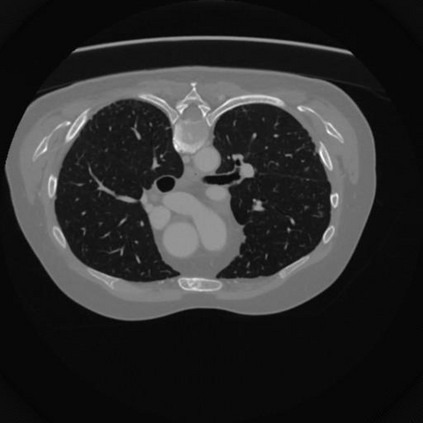

Sparse-view computed tomography (CT) -- using a small number of projections for tomographic reconstruction -- enables much lower radiation dose to patients and accelerated data acquisition. The reconstructed images, however, suffer from strong artifacts, greatly limiting their diagnostic value. Current trends for sparse-view CT turn to the raw data for better information recovery. The resultant dual-domain methods, nonetheless, suffer from secondary artifacts, especially in ultra-sparse view scenarios, and their generalization to other scanners/protocols is greatly limited. A crucial question arises: have the image post-processing methods reached the limit? Our answer is not yet. In this paper, we stick to image post-processing methods due to great flexibility and propose global representation (GloRe) distillation framework for sparse-view CT, termed GloReDi. First, we propose to learn GloRe with Fourier convolution, so each element in GloRe has an image-wide receptive field. Second, unlike methods that only use the full-view images for supervision, we propose to distill GloRe from intermediate-view reconstructed images that are readily available but not explored in previous literature. The success of GloRe distillation is attributed to two key components: representation directional distillation to align the GloRe directions, and band-pass-specific contrastive distillation to gain clinically important details. Extensive experiments demonstrate the superiority of the proposed GloReDi over the state-of-the-art methods, including dual-domain ones. The source code is available at https://github.com/longzilicart/GloReDi.